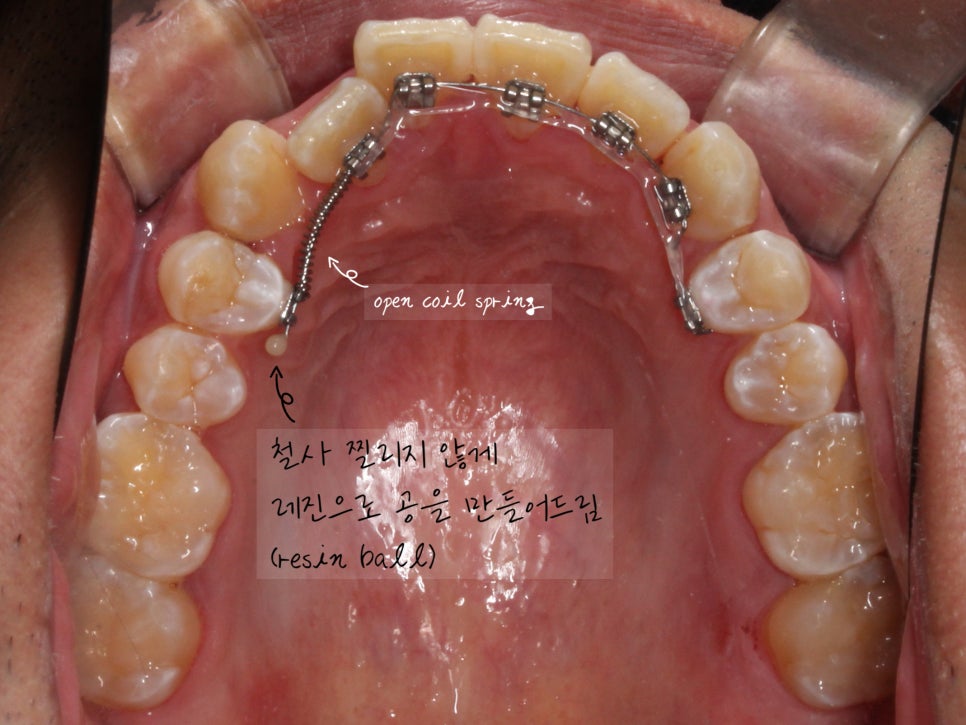

치아 안쪽으로 교정기를 부착한 모습입니다.

2D교정 진행한지 1달째 되는 날 촬영했습니다.

아래 치아는 배열될 공간을 만들기 위해

치간 삭제를 동반하여 치료하고 있었고

#12 치아가 나올 수 있도록

안쪽에 open coil 을 넣어둔 상태입니다.

*open coil spring : 공간을 벌리기 위해 쓰는 스프링

open coil spring을 넣어둔 곳은

그만큼 치아가 공간이 생길 곳이라

일부러 끝에 철사를 길게 남겨두었습니다.

공간이 생길 동안 환자분께서 불편하시지 않도록

resin ball을 달아둔 상태입니다.

*Resin ball : 레진으로 공처럼 둥글게 처리해 주는 것

간혹 resin ball이 떨어지시기도 하셔서

wax를 넉넉히 챙겨드렸습니다.